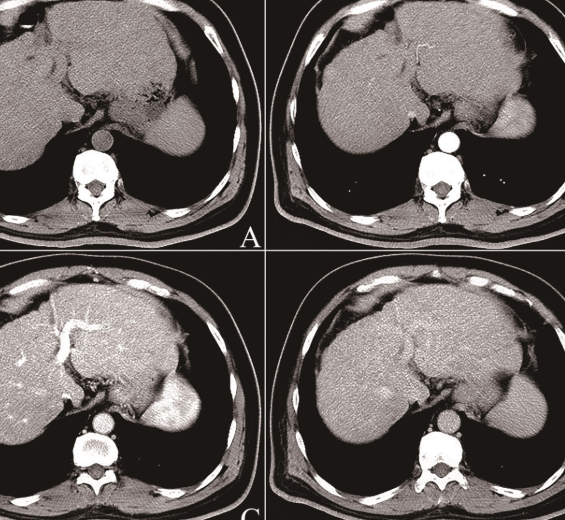

생활 중심 관리를 통해 결절 변화가 없거나 안정적이라면, 정기 검진을 지속하면서 변화 여부를 지켜보는 것이 바람직합니다. 하지만 결절의 크기가 커지거나 형태가 불규칙해지는 경우, 전문의 상담을 통해 조직검사나 정밀 영상검사를 고려할 수 있습니다.

전문의와 논의할 수 있는 평가 항목으로는 결절의 크기, 경계 모양, 내부 구조, 혈관성 여부 등이 있으며, 필요한 경우 생검이나 추가 진단을 받을 수 있습니다. 치료 방법은 수술적 접근, 비수술적 관찰, 혈관색전술, 또는 약물적 접근(연구 단계)에 따라 달라질 수 있으니, 반드시 전문의와 충분히 상의해야 합니다.